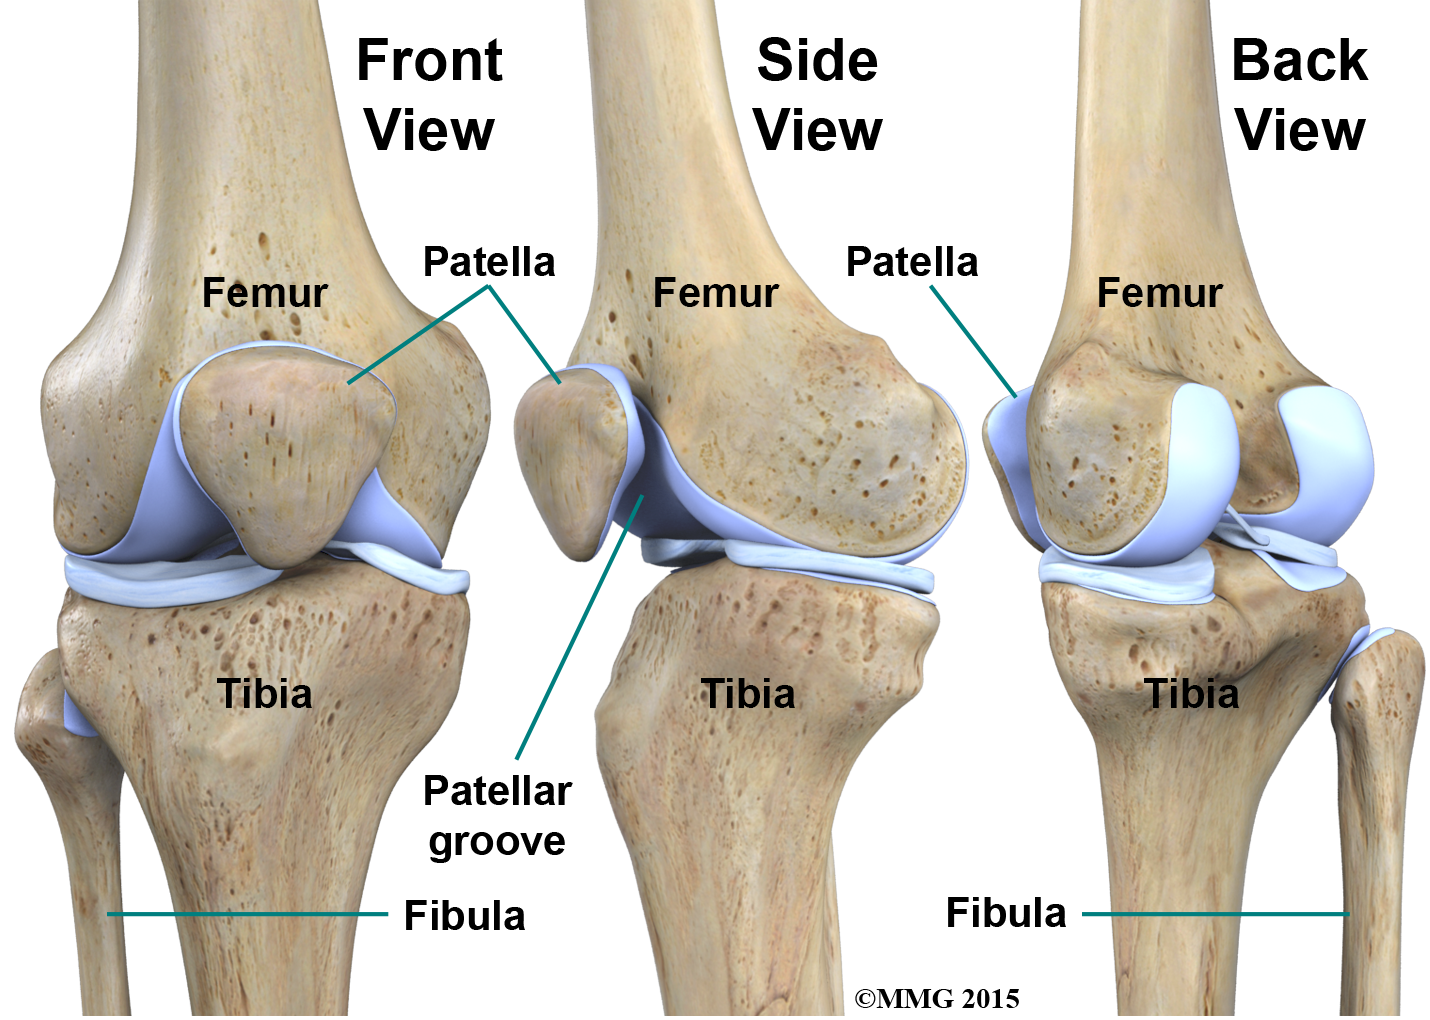

The knee is the meeting place of two important bones in the leg, the femur (the thighbone) and the tibia (the shinbone). The patella (or kneecap, as it is commonly called) is made of bone and sits in front of the knee.

The end of the femur joins the top of the tibia to create the knee joint. Two round knobs called femoral condyles are found on the end of the femur. These condyles rest on the top surface of the tibia. This surface is called the tibial plateau. The outside half (farthest away from the other knee) is called the lateral tibial plateau, and the inside half (closest to the other knee) is called the medial tibial plateau. The patella glides through a special groove formed by the two femoral condyles called the patellofemoral groove.

The smaller bone of the lower leg, the fibula, never really enters the knee joint. It does have a small joint that connects it to the side of the tibia. This joint normally moves very little.

Bones and Joints of the Knee